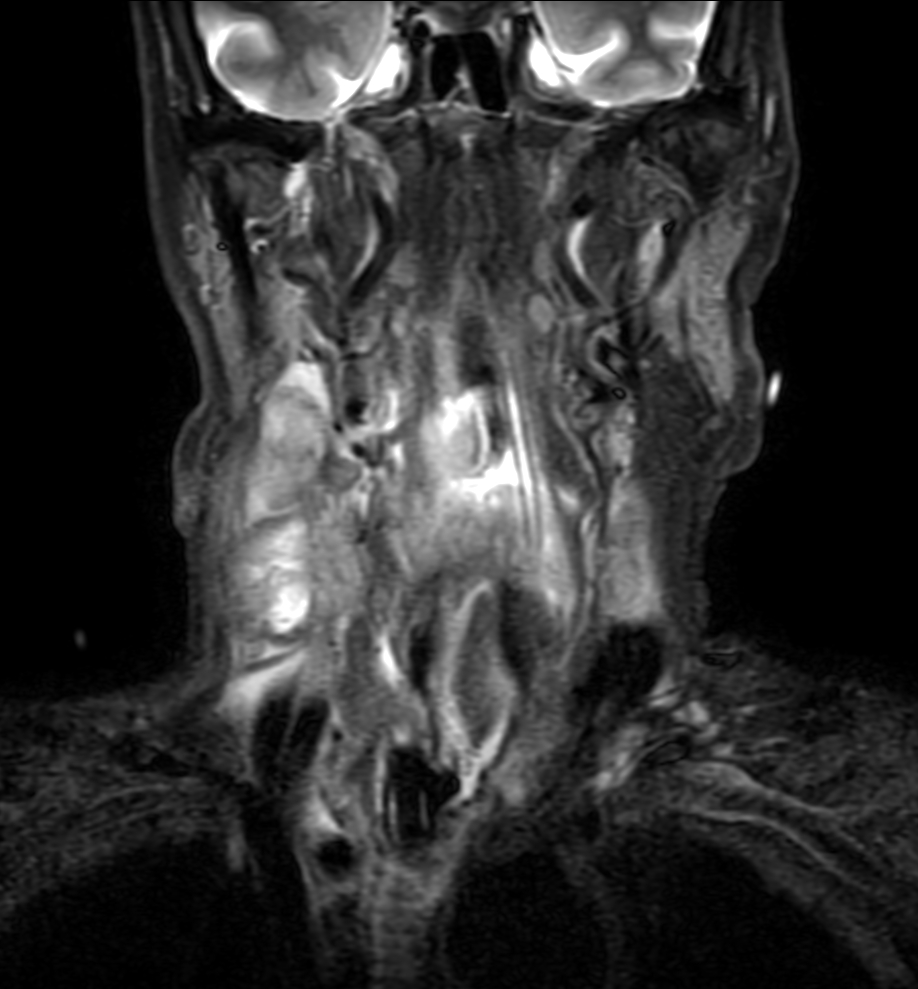

Coronal STIR TSE